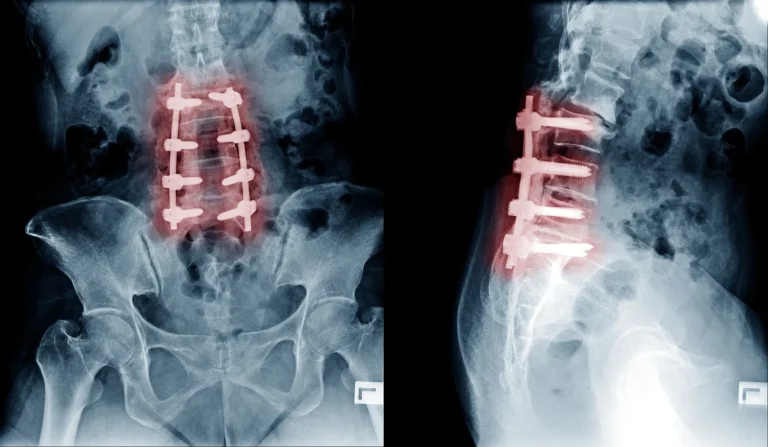

X-ray images showing spinal fusion with metal screws in the lower back.

Back Pain Becomes Worse

X-ray showing spinal hardware in the lower back from front and side views.

Additional Surgery Necessary